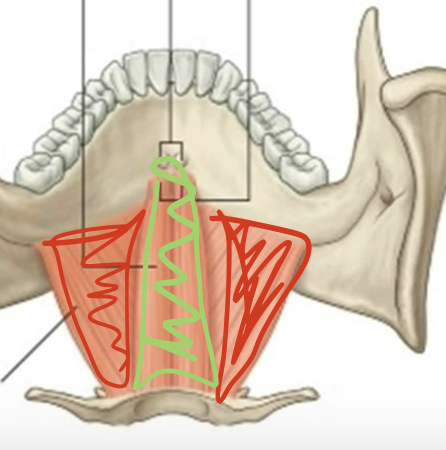

What is the muscle in red?

Mylohyoid (elevate hyoid, depress mandible)

What is this muscle in green?

Geniohyoid (elevate hyoid, depress mandible)